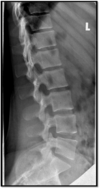

Lateral Lumbar Spine Criteria

- open disc spaces and foramina (angle) - Superimposed pedicles (rotation)

26

SID and CR placement for lateral Lumbar spine with curve

**always direct the CR into the concave side if a curve is present and use short SID for beam divergence**

27

increase caudad angle used to superimpose vertebral body edges - right 12th rib is more anterior thus need to rotate right side posteriorly

28

- not perp to spine - cant tell how to fix because cant see ribs **cert exam : build up top of spine on sponge**